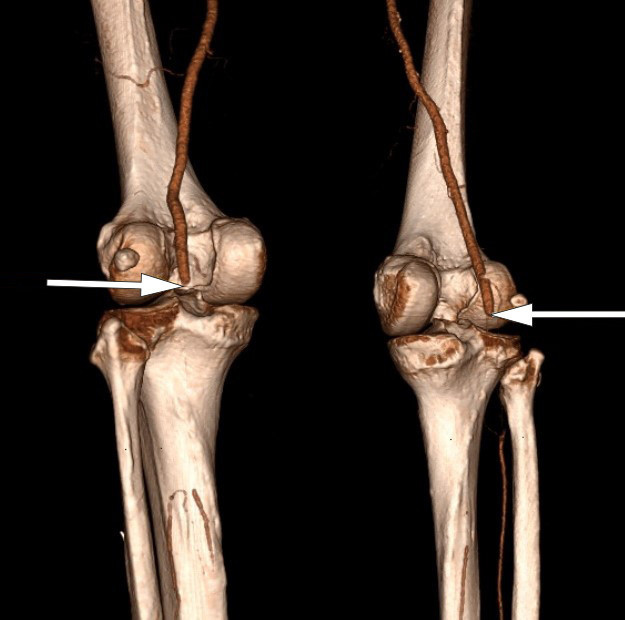

PCR-test for covid-19 ved innkomst var negativ, og pasienten hadde ingen respiratoriske symptomer. CT-angiografi viste manglende kontrastfylling fra begge aa. poplitea i kneleddsspalten (figur 1). Han hadde også okklusjoner distalt, men stedvis kontrastfylling av leggarterier, forenlig med tromboser i begge underekstremiteter. Pasienten fikk 5 000 IE dalteparin og ble deretter overflyttet til et regionssykehus.

Ved ankomst regionssykehuset var pasienten respiratorisk og sirkulatorisk stabil. Venstre underekstremitet hadde kliniske tegn på akutt iskemi med smerte og redusert sensibilitet, men bevart motorikk. Høyre underekstremitet hadde i løpet av dagen blitt gradvis bedre med bevart sensibilitet og motorikk, men var fortsatt kald perifert. Pasienten ble operert i generell narkose med trombektomi av bilaterale aa. poplitea og leggarterier. Postoperativt var begge ben velsirkulerte.

Etter noen timer ble høyre fot igjen kjølig, smertefull og uten dopplersignal i fotarterier. Pasienten ble derfor reoperert. Det ble på ny gjort utrenskning av leggarterier med funn av rikelig med trombemasser.